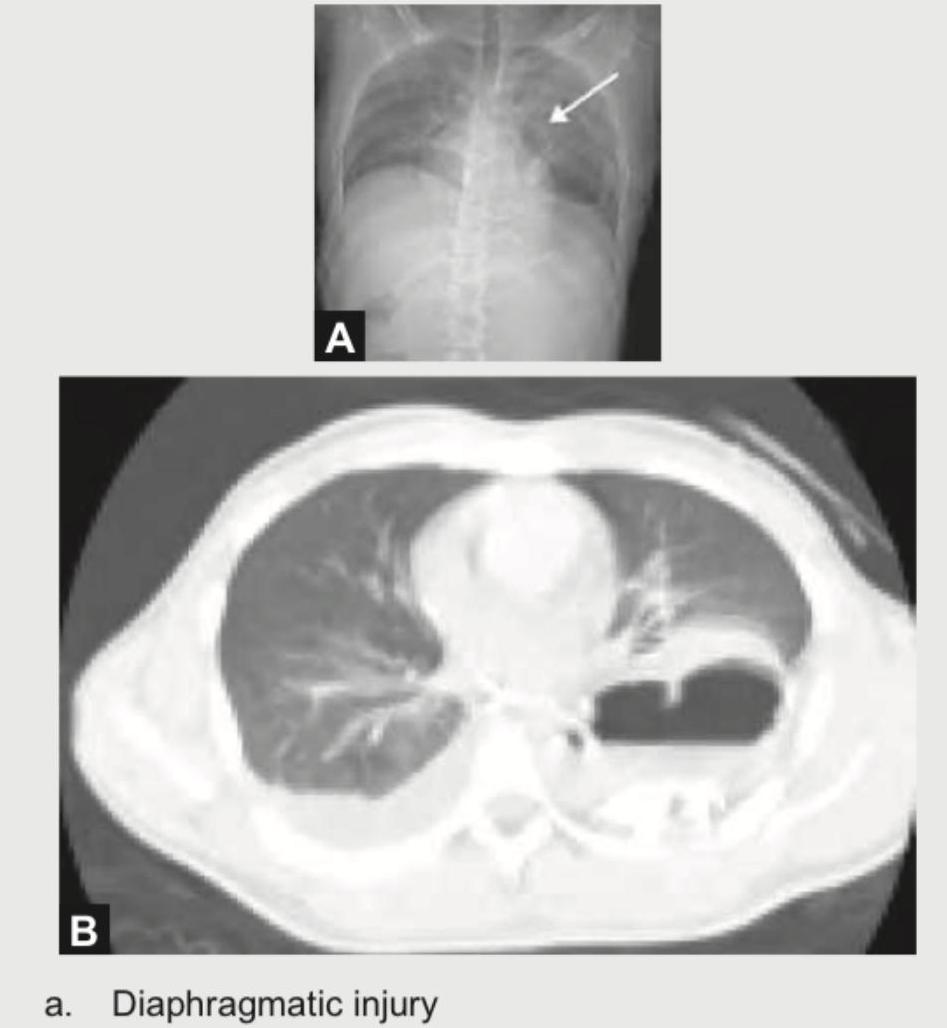

Explanation: ***Diaphragmatic injury*** - The chest X-ray (**A**) shows opacification in the left lower lung field with a **raised hemidiaphragm**, and the CT scan (**B**) reveals **herniated bowel loops** and **stomach** (appearing as a gas-filled structure) in the left hemithorax. - The insertion of an **NG tube and contrast injection** to confirm the stomach's presence in the chest is a classical diagnostic approach for **diaphragmatic rupture** following penetrating trauma. *Hemothorax* - Hemothorax would primarily show **fluid collection** in the pleural space, which appears homogeneous on CT, typically without specific organ herniation. - While plausible with penetrating trauma, the images specifically show **organ herniation**, not just blood. *Pneumothorax* - Pneumothorax is characterized by **air in the pleural space**, resulting in lung collapse and a visible pleural line. - The images show solid/fluid-filled structures (bowel, stomach) rather than free air and lung collapse. *Cardiac Tamponade* - Cardiac tamponade involves **fluid accumulation in the pericardial sac**, leading to impaired cardiac filling. - This condition primarily affects heart function and is identified by specific echocardiographic findings, which are not depicted in these chest imaging studies.